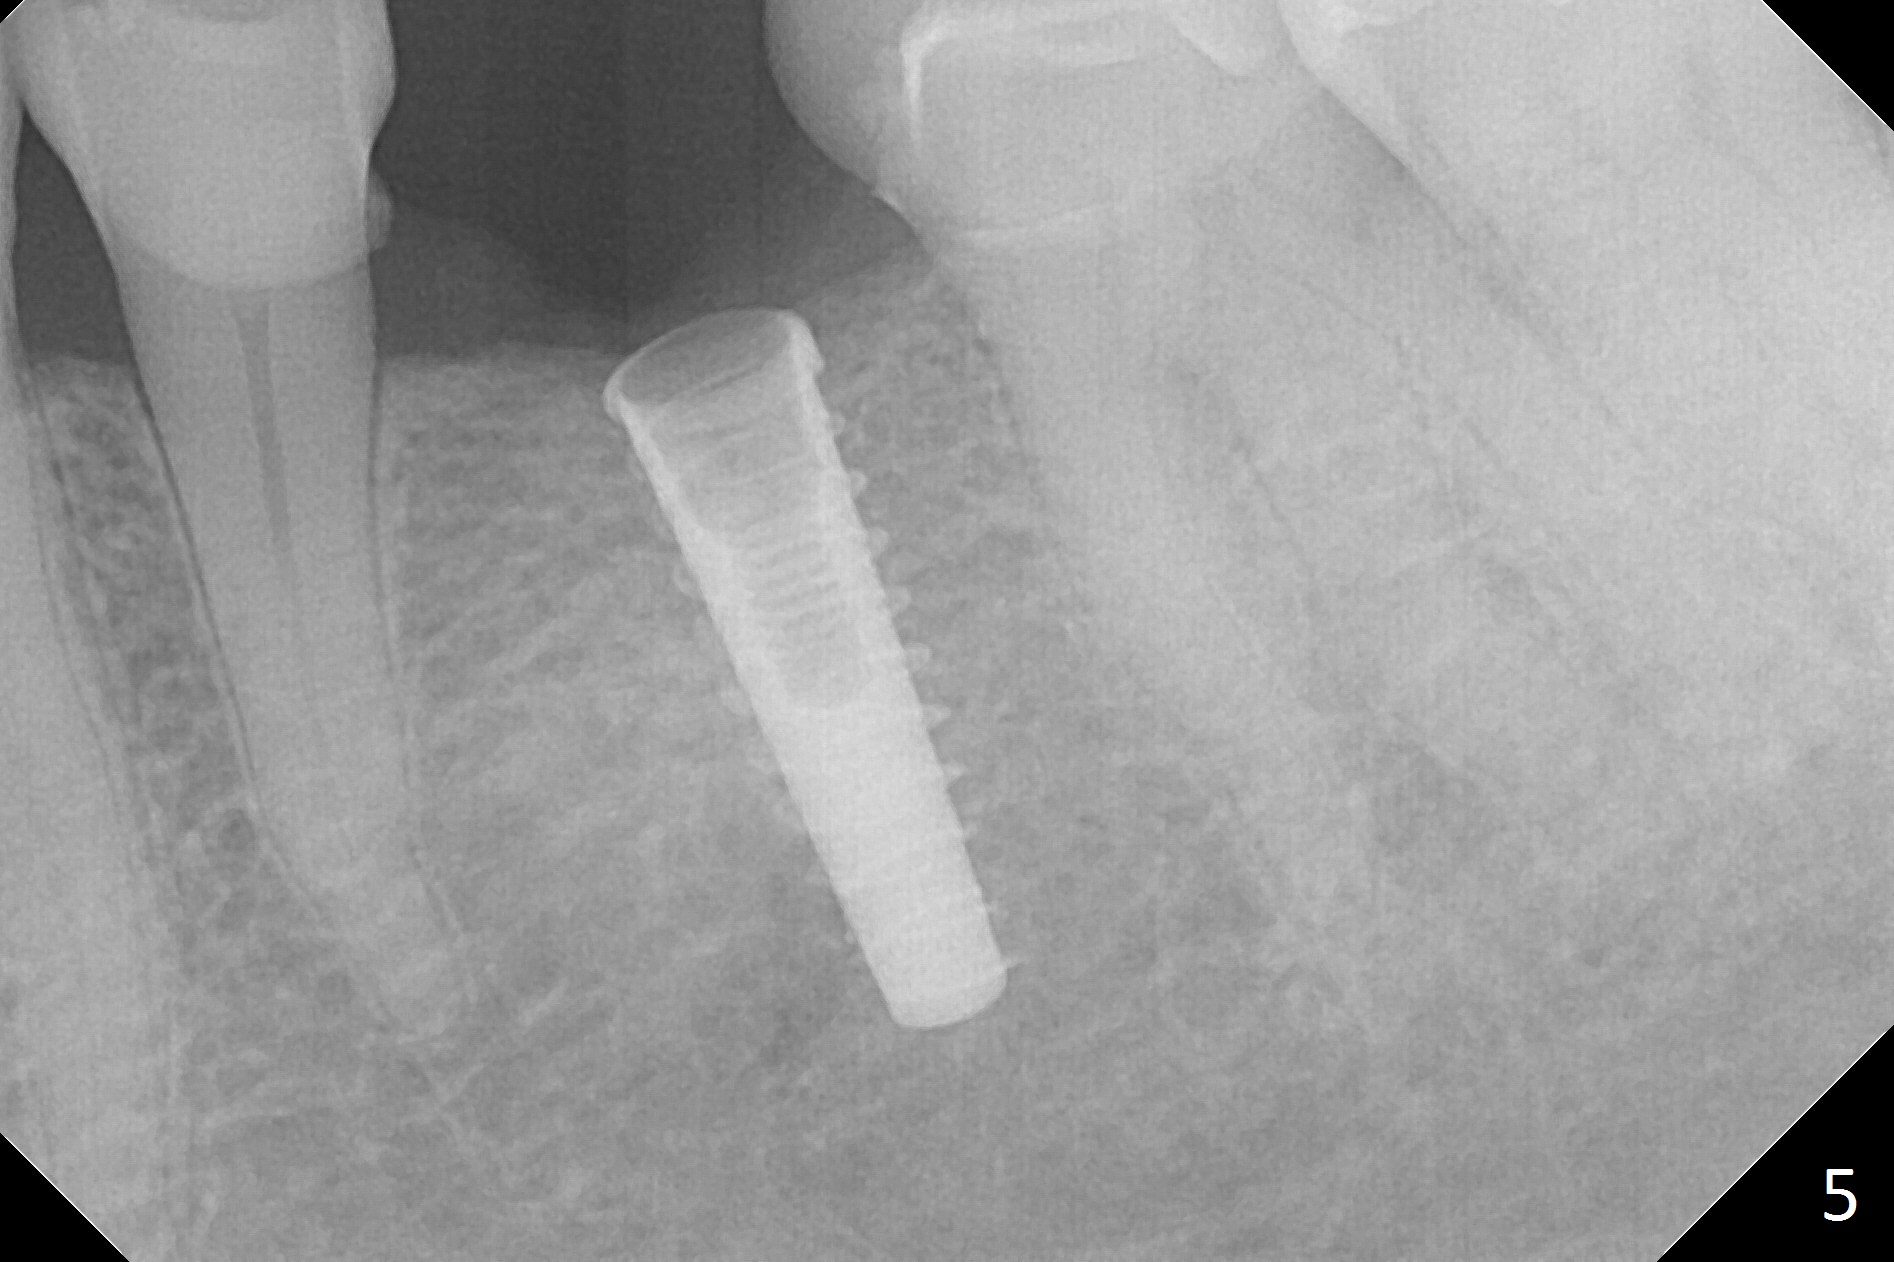

Initial osteotomy with 1.6 mm drill for 11 mm seems to be distal (Fig.1).  The trajectory should be changed as shown by the black line in Fig.2; the drawback would be close to the Mental Loop (red line).  Fortunately the trajectory is changed, but not so much as to be close the Loop when a 4x11 mm dummy implant is placed (Fig.3).   When a 4x13 mm IBS is placed with 46 Ncm, there is clearance from the Loop (Fig.4-6).  In fact there is no postop paresthesia.  The main point is no block anesthesia.  Infiltration anesthesia is administered with 34 mg Xylocaine with 17 mcg Epinephrine.  The patient experiences dull pain when the implant is placed (Fig.4-6).  After further anesthesia with 68 mg Septocaine, 17 mcg Epinephrine, the implant is torqued for a few turns (still with some discomfort).  Finally autogenous bone with Osteogen is placed around the implant following placement of a 4.5x4(2) mm abutment.  To reduce anxiety, a shorter implant should have been used. The patient complains of cold sensitivity in the lower left quadrant 4 months postop (Fig.7): the implant apparently close to the Mental Loop.  Without an immediate provisional, the gingiva around the abutment is healthy.